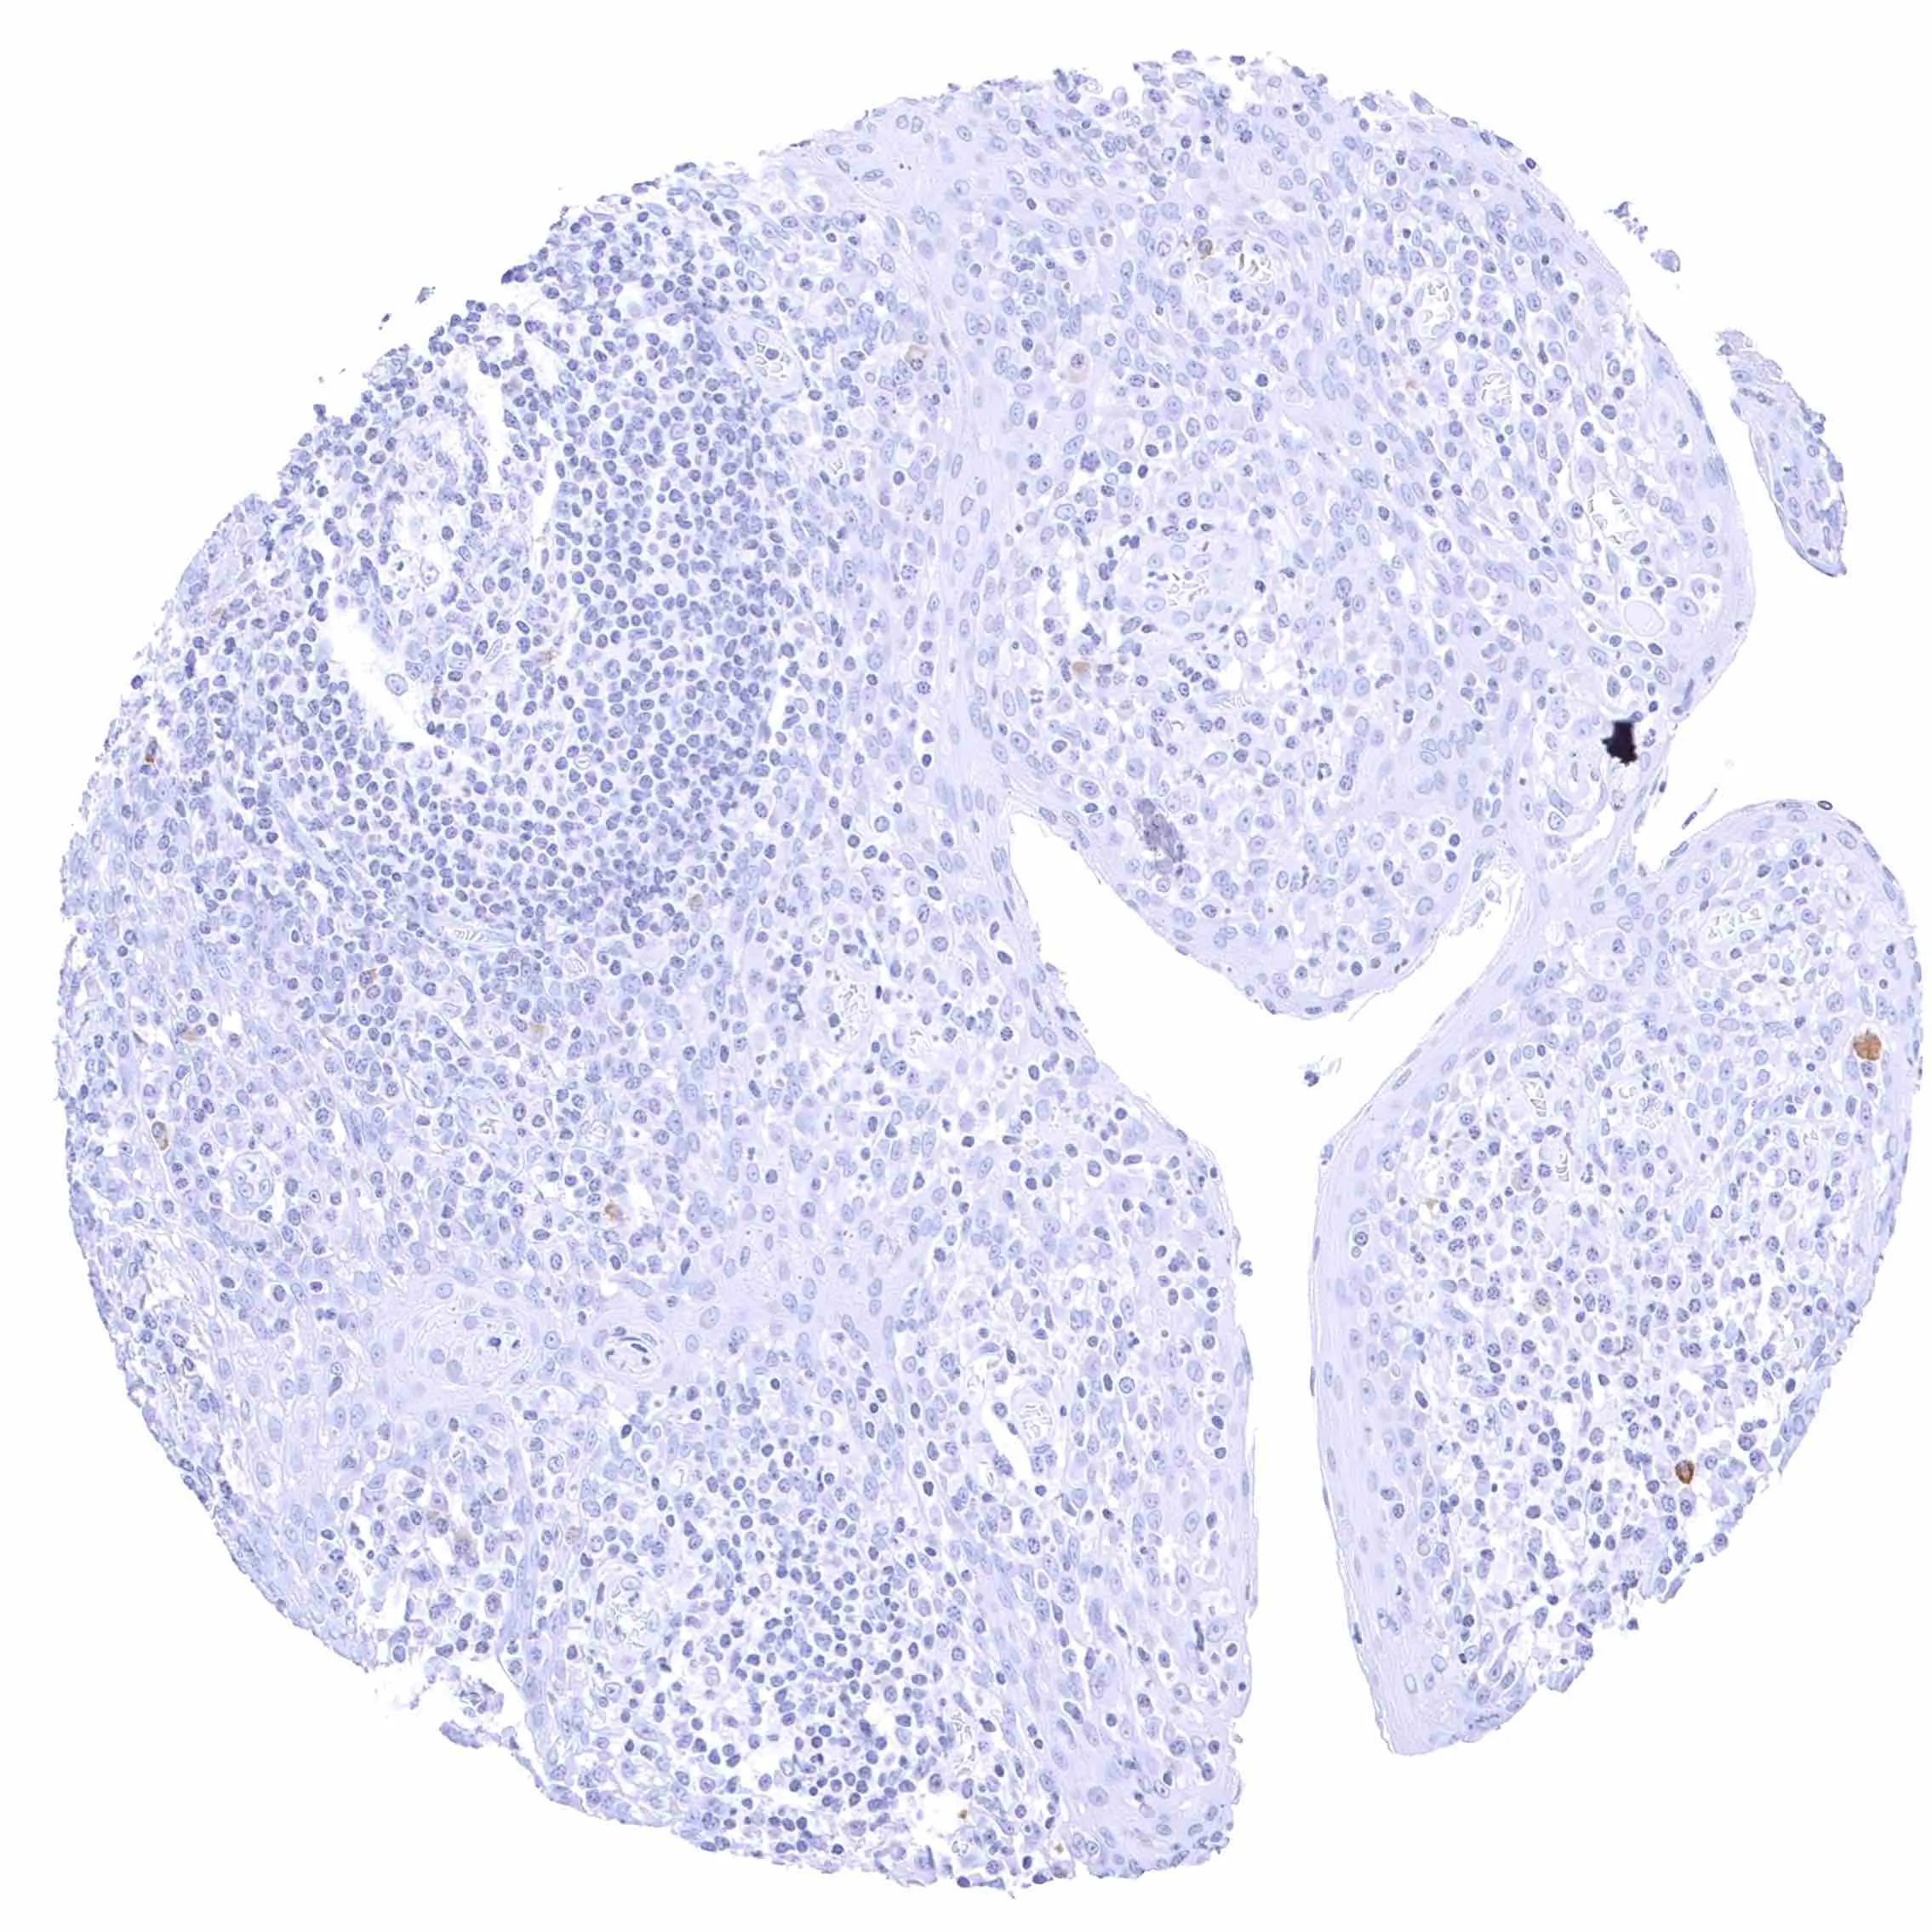

Lymph node

Thymus

Tonsil